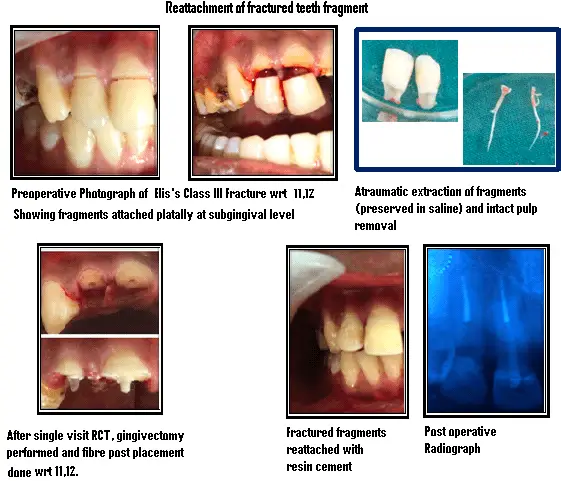

Fragment Reattachment After Traumatic Injury

A 22 year old Patient reported with a history of trauma causing fracture of upper anterior teeth few hours back , after thorough examination , a diagnosis of Ellis class III fracture in relation to 11 and 12 was made .Fractured segments were attached palatally at subgingival level . Intensive treatment plan was charted, and after acquiring patient’s consent, reattachment of the fractured segment after root canal treatment was planned on the same day . Fractured segments were extracted atraumatically and placed in normal saline and Single sitting RCT with fibre post was done to relieve the pain. After that gingivectomy was performed in relation to same teeth and fractured segments were reattached to their corresponding position with resin cement . Follow up was done after a month and patient was symptom free and happy.